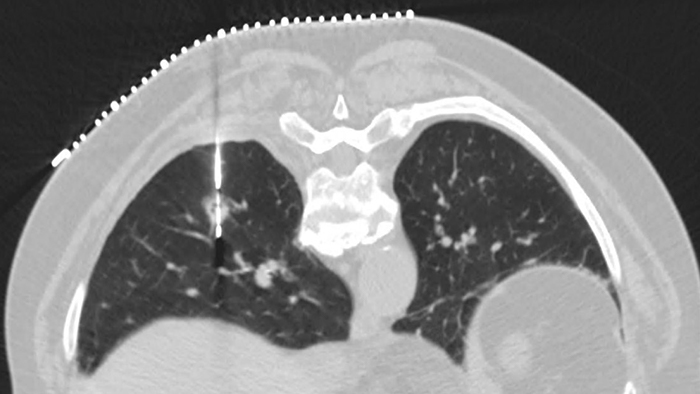

Experience the image quality that can be achieved with simultaneously up to 80% less dose, up to 85% less noise and up to 60% improved low-contrast detectability.3 Precise Image has a familiar image appearance that closely resembles filtered back projection (FBP). You’ll also see best-in-class low-contrast resolution.

Slide the bar to compare images without and with Precise Image.